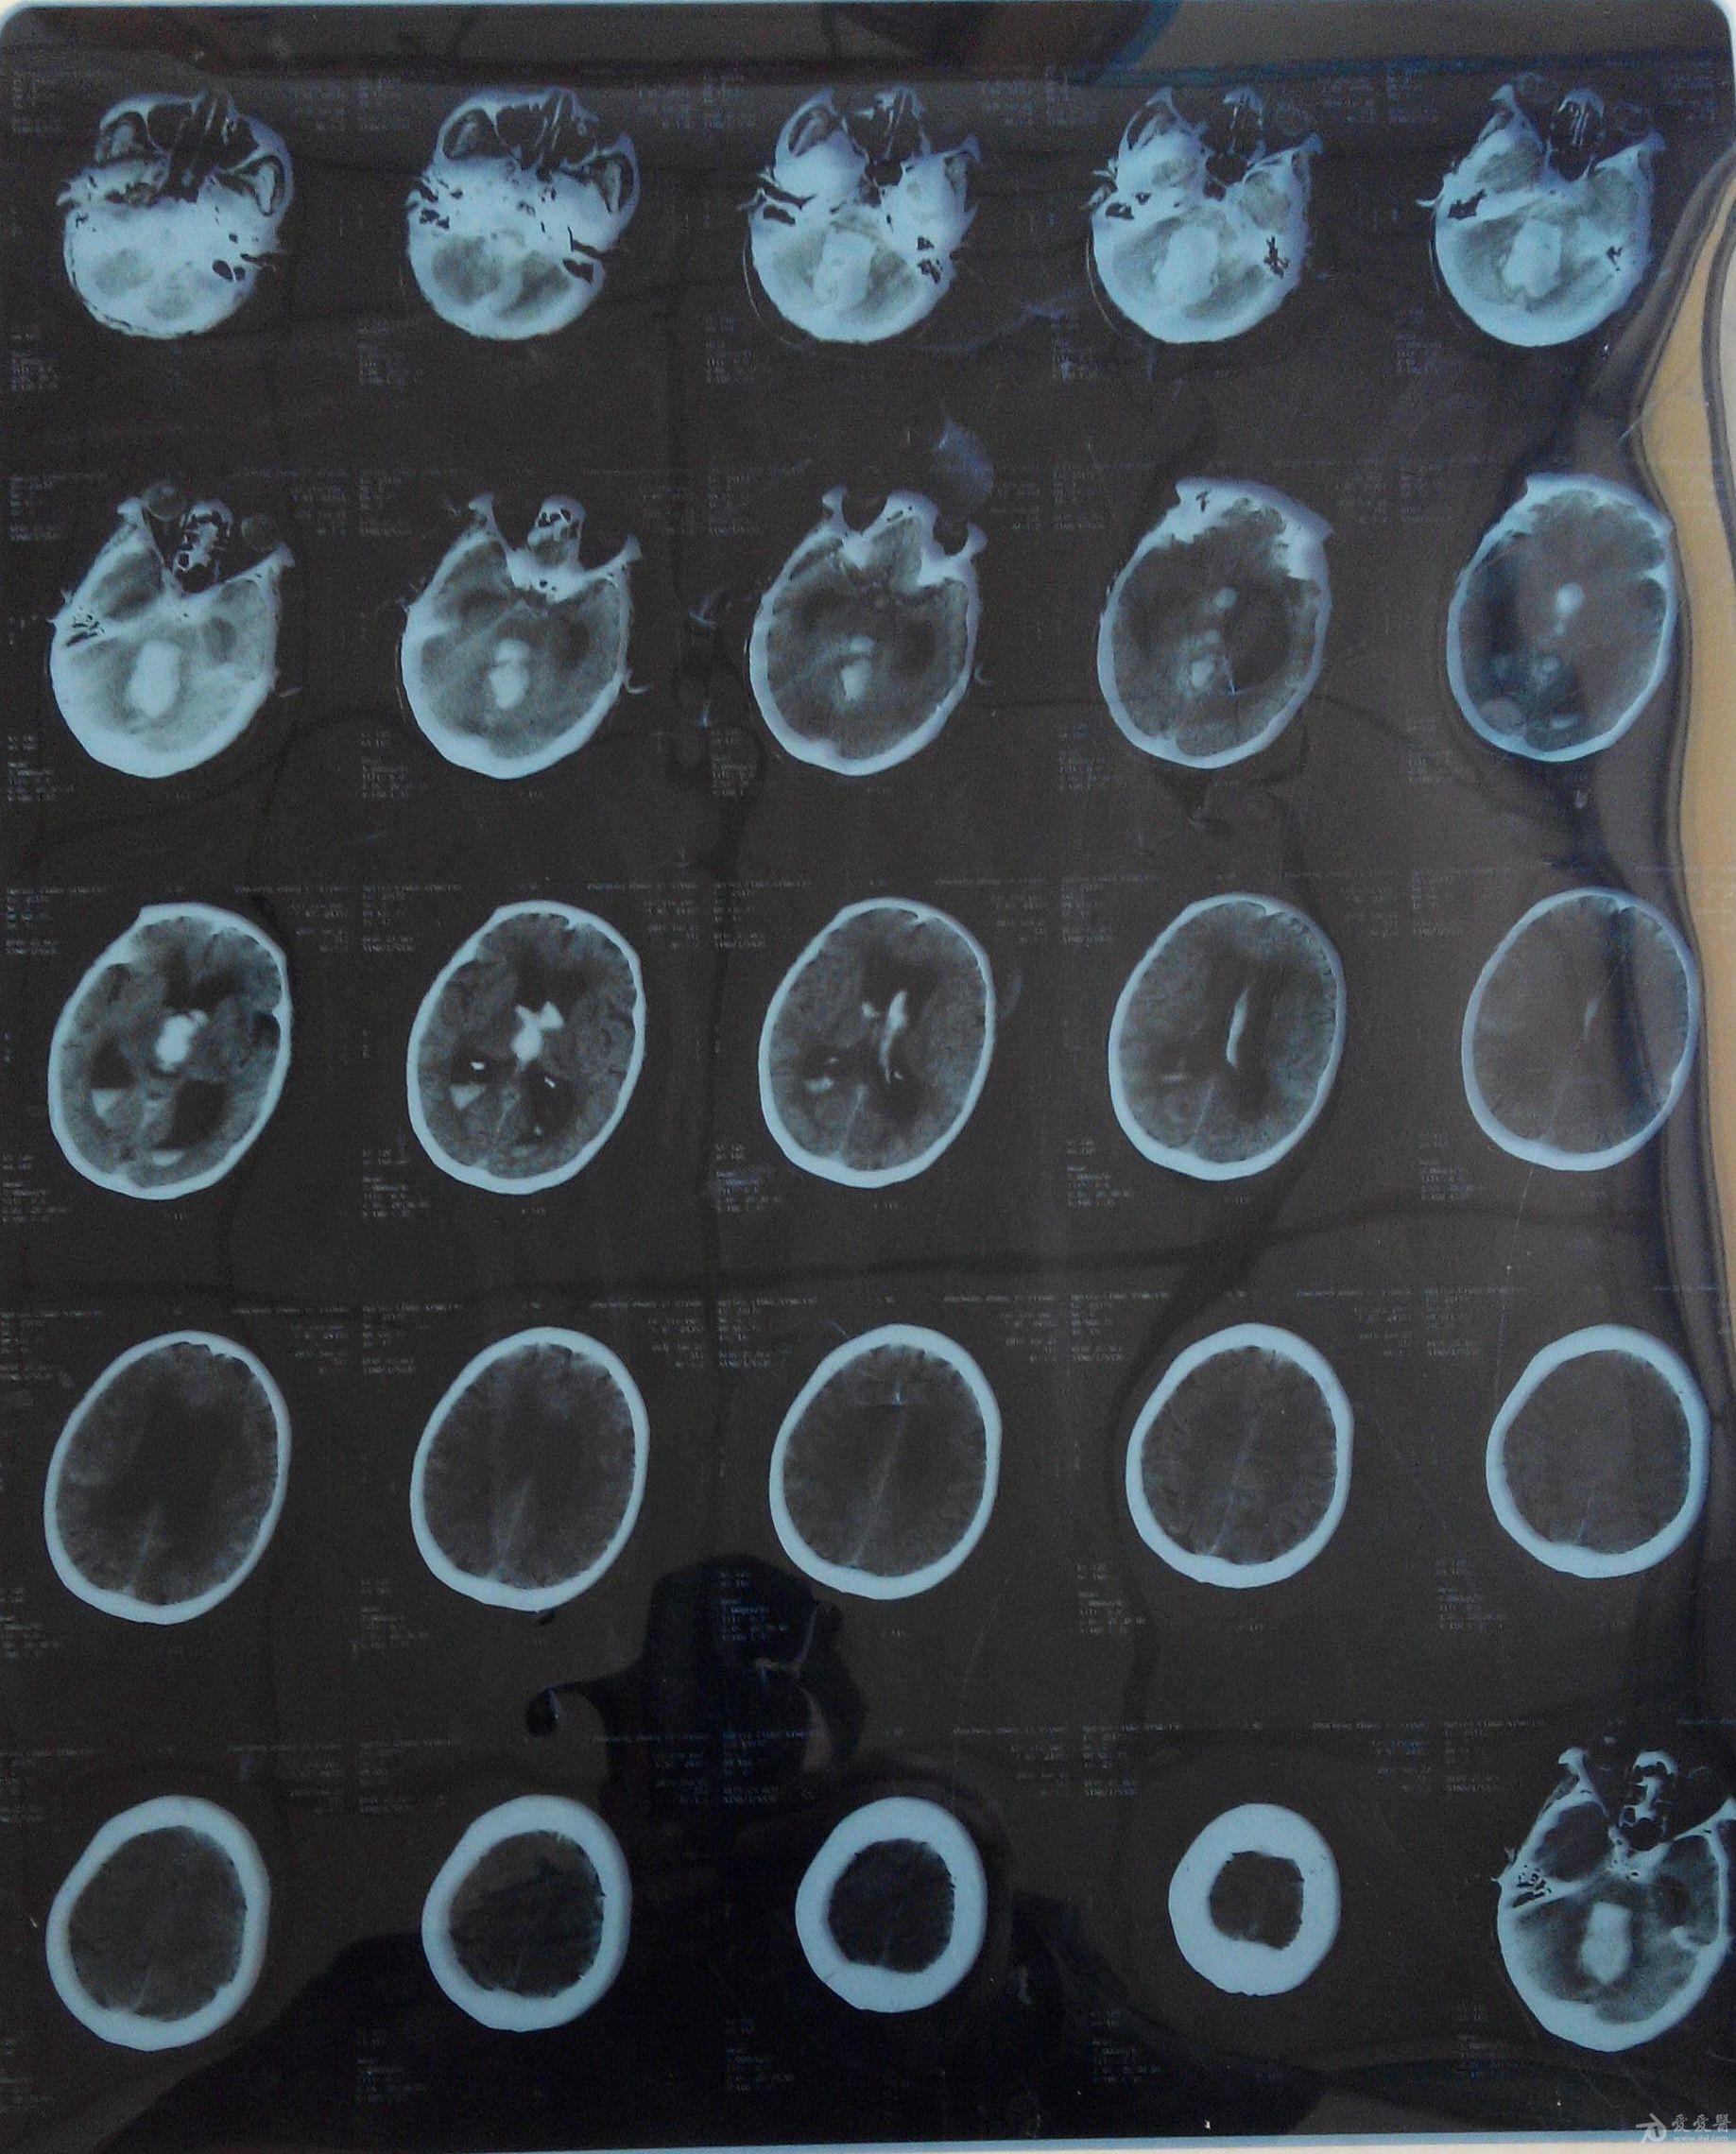

患者:刘春凤,女,43岁,右侧基底节区脑出血

图片尺寸2000x2667